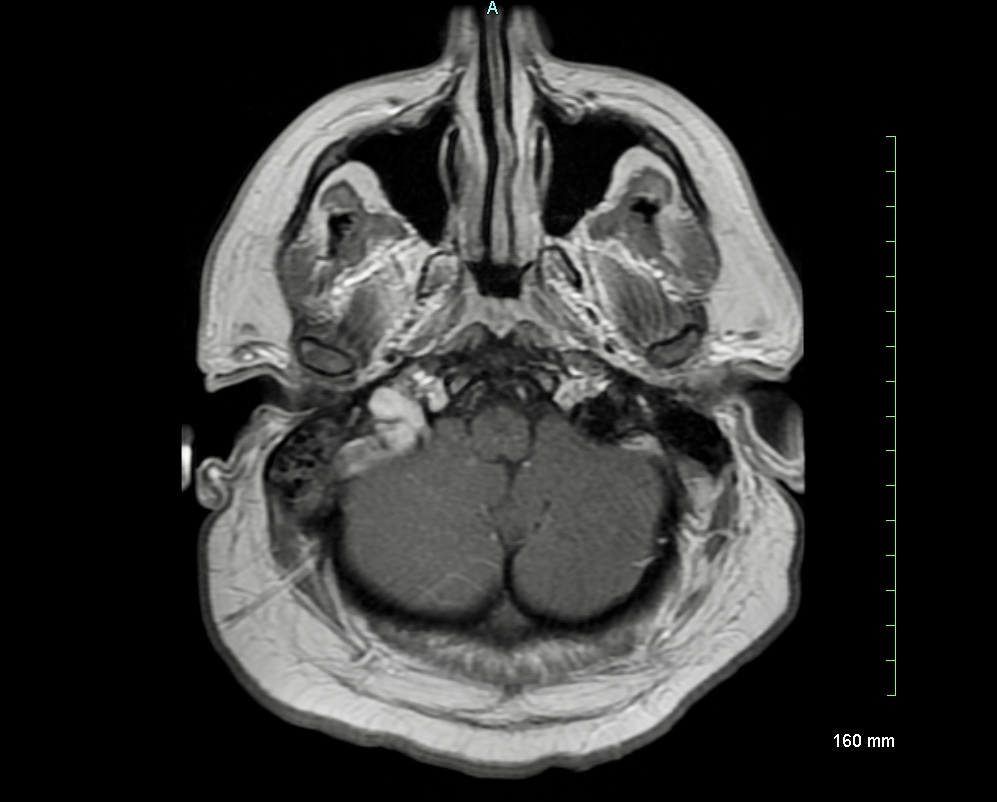

Case Presentation: A 29-year-old male presented with a new onset focal seizure and dull persistent right sided headaches for 2 weeks. Physical exam was negative for any focal neurological deficit except for a diffuse erythematous rash involving trunk and his extremities, bilateral conjunctival injection and mild confusion. An urgent CT head revealed a small acute parenchymal hemorrhage in the right inferior parietal lobe with a small amount of associated SAH. A subsequent CTA ruled out vascular malformations, but revealed dural venous sinus thrombosis involving right transverse sinus, sigmoid sinus, jugular bulb, and a portion of right IJV. MRI confirmed the findings. Lab results were pertinent for WBC count 3.5, CRP 1 and mild proteinuria with WBC casts. Extensive thrombophilia work-up was negative, yet autoimmune blood work revealed positive ANA (>1:640), dsDNA:72, low C3 and C4 levels, negative APLA and negative RF. EEG did not show any new epileptiform activity. Patient met the diagnostic criteria of SLE as per ACR. He was started on oral prednisone, hydroxychloroquine and therapeutic heparin, and gradually transitioned to warfarin with INR goal of 2-3.

Discussion: Cerebral venous sinus thrombosis (CVST) is an uncommon manifestation of neuropsychiatric lupus and is usually associated with secondary antiphospholipid antibody syndrome (APLA). CVST as a presenting feature in a male patient with systemic lupus erythematosus (SLE) with negative APLA is particularly rare (1,2). We report the case of a young male with CVST as the initial form of presentation of his SLE. He also has negative antiphospholipid antibodies.

Dural venous sinus thrombosis is a relatively rare complication of SLE, and even more rare to be a presenting diagnosis (3). In most cases, it is associated with anti phospholipid antibody syndrome but rarely presents without secondary APLA (4). CVST usually occurs in active lupus patients and has been associated with a higher SLEDAI score (SLE disease activity score). Etiology of CVST is multifactorial in SLE including vasculitis due to immune complexes along with prothrombotic state due to APLA (5). CVT can present as headaches, intra cranial hypertension, altered mental status, seizures or a local mass.